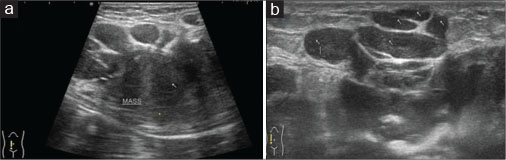

A 40-year old male patient presented with swelling over the anterior abdominal wall on the right side in lower abdomen for 1 month which was rapidly increasing in size. There was a history of weight loss. The mass was painless. The ultrasonography showed a large, well-defined solid mass with lobulated outlines in anterior abdominal wall in the right paraumbilical and hypogastric region [Figure 1]. The mass was seen in the subcutaneous plane, causing extrinsic compression on adjoining right rectus abdominis and external oblique muscle. It was predominantly hypoechoic with small areas of the necrosis in its center and showed mild vascularity on color Doppler. No calcification was seen. Plain and contrast enhanced computed tomography (CT)-scan of the abdomen and pelvis was performed. A large, well defined solid mass with lobulated outline measuring approximately 96 mm × 38 mm × 98 mm in transverse, anteroposterior and craniocaudal dimension was noted in the anterior abdominal wall on the right side in right iliac region extending to hypogastric region. It was slightly hypodense with respect to muscle on the plain study with a CT value of 35–45 HU and showed a mild heterogeneous enhancement in contrast study (CT value 55–65 HU). No calcification was noted. The mass was in subcutaneous plane and was extending anteriorly up the skin. Posteriorly, it was causing mass effect on the right rectus abdominus and adjoining external oblique and internal oblique muscles which were compressed and displaced posteriorly with obliteration of intervening fat planes [Figure 2]. An enhancing vessel was noted in the right rectus abdominus extending into the mass suggestive of neovascularity. No intra-abdominal extension was noted. Rest of the abdominal wall appeared normal. No hepatic or adrenal metastases, intra-abdominal lymphadenopathy noted. On magnetic resonance imaging (MRI), the mass appeared slightly hyperintense with respect to muscle on T1-weighted image, heterogeneously hyperintense on T2-weighted image (T2WI), and hyperintense on short tau inversion recovery and showed restricted diffusion on diffusion-weighted imaging with low apparent diffusion coefficient (ADC) values (ADC = 800). It was causing mass effect on the right rectus abdominus and adjoining external oblique and internal oblique muscles [Figure 3] [4] [5] [6].

| Figure 1: Ultrasound of the anterior abdominal wall with linear probe showing well-defned solid hypoechoic mass with lobulated outlines in the right iliac fossa in subcutaneous plane (a) causing extrinsic compression and posterior displacement of abdominal wall muscles (b)